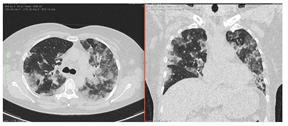

КТ имеет высокую чувствительность в выявлении изменений в легких, характерных для COVID-19. Применение КТ целесообразно для первичной оценки состояния ОГК у пациентов с тяжелыми прогрессирующими формами заболевания, а также для дифференциальной диагностики выявленных изменений и оценки динамики процесса. КТ позволяет выявить характерные изменения в легких у пациентов с COVID-19 еще до появления положительных лабораторных тестов на инфекцию с помощью МАНК. В то же время, КТ выявляет изменения легких у значительного числа пациентов с бессимптомной и легкой формами заболевания, которым не требуется госпитализация. Результаты КТ в этих случаях не влияют на тактику лечения и прогноз заболевания при наличии лабораторного подтверждения COVID-19. Поэтому массовое применение КТ для скрининга асимптомных и легких форм болезни не рекомендуется.

4. Все выявляемые при лучевых исследованиях признаки, включая КТ-симптомы, не являются специфичными для какого-либо вида инфекции и не позволяют установить этиологический диагноз. Вне клинической (эпидемической) ситуации они не позволяют отнести выявленные изменения к пневмонии COVID-19 и дифференцировать их с другими пневмониями и невоспалительными заболеваниями. Данные лучевого исследования не заменяют результаты обследования на РНК SARS-CoV-2. Отсутствие изменений при КТ не исключают наличие COVID-19 и возможность развития пневмонии после проведения исследования.